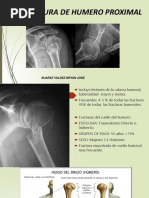

SE ENTIENDE POR FRACTURA DEL

EXTREMO PROXIMAL DEL HUMERO A

LAS QUE OCURREN EN LA CABEZA , EL

CUELLO , LAS TUBEROSIDADES Y LA

PARTE PROXIMAL DE LA DIAFISIS

HASTA EL BORDE INFERIOR DE LA

INSERCION DEL PECTORAL MAYOR

 Las fracturas del humero proximal

pueden separarse en 4 grandes

fragmentos:

 Porción superior del humero, proximal

al cuello anatómico

 Tubérculo menor (troquín)

 Tubérculo mayor (troquiter)

 Cuello quirúrgico (es la más común)

CLASIFICACION

DE NEER

• NEER 1: Fractura no desplazada. Puede

ser en tres segmentos pero ninguno

desplazado (80%).

• NEER 2: Fractura en dos partes, un

segmento desplazado de los otros tres

(10%).

• NEER 3: Fractura de tres partes, dos

segmentos desplazados (3%).

• NEER 4: Fractura en cuatro partes, tres o

cuatro segmentos desplazados (4%).